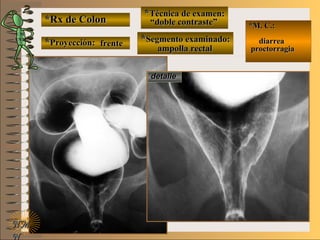

*Rx de Estómago*Rx de Estómago

**Proyección:Proyección:

**Técnica de examen:Técnica de examen:

A-A-

B-B-

C-C-